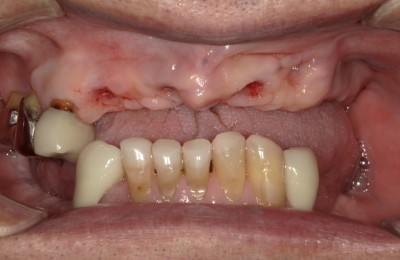

CASE01インプラント

-

Before

After

| 主訴 | 入れ歯以外の方法でしっかり咬みたい。 |

|---|---|

| 治療方法 | インプラントを6本埋入し、その上部をセラミックで作りしっかり咬めるようにした。 |

| 治療期間 | 約5カ月 |

| リスク | メンテナンスをしないことによるインプラント周囲炎、上部セラミックの破折。 |

| 費用 | 3,476,000円(税込) |